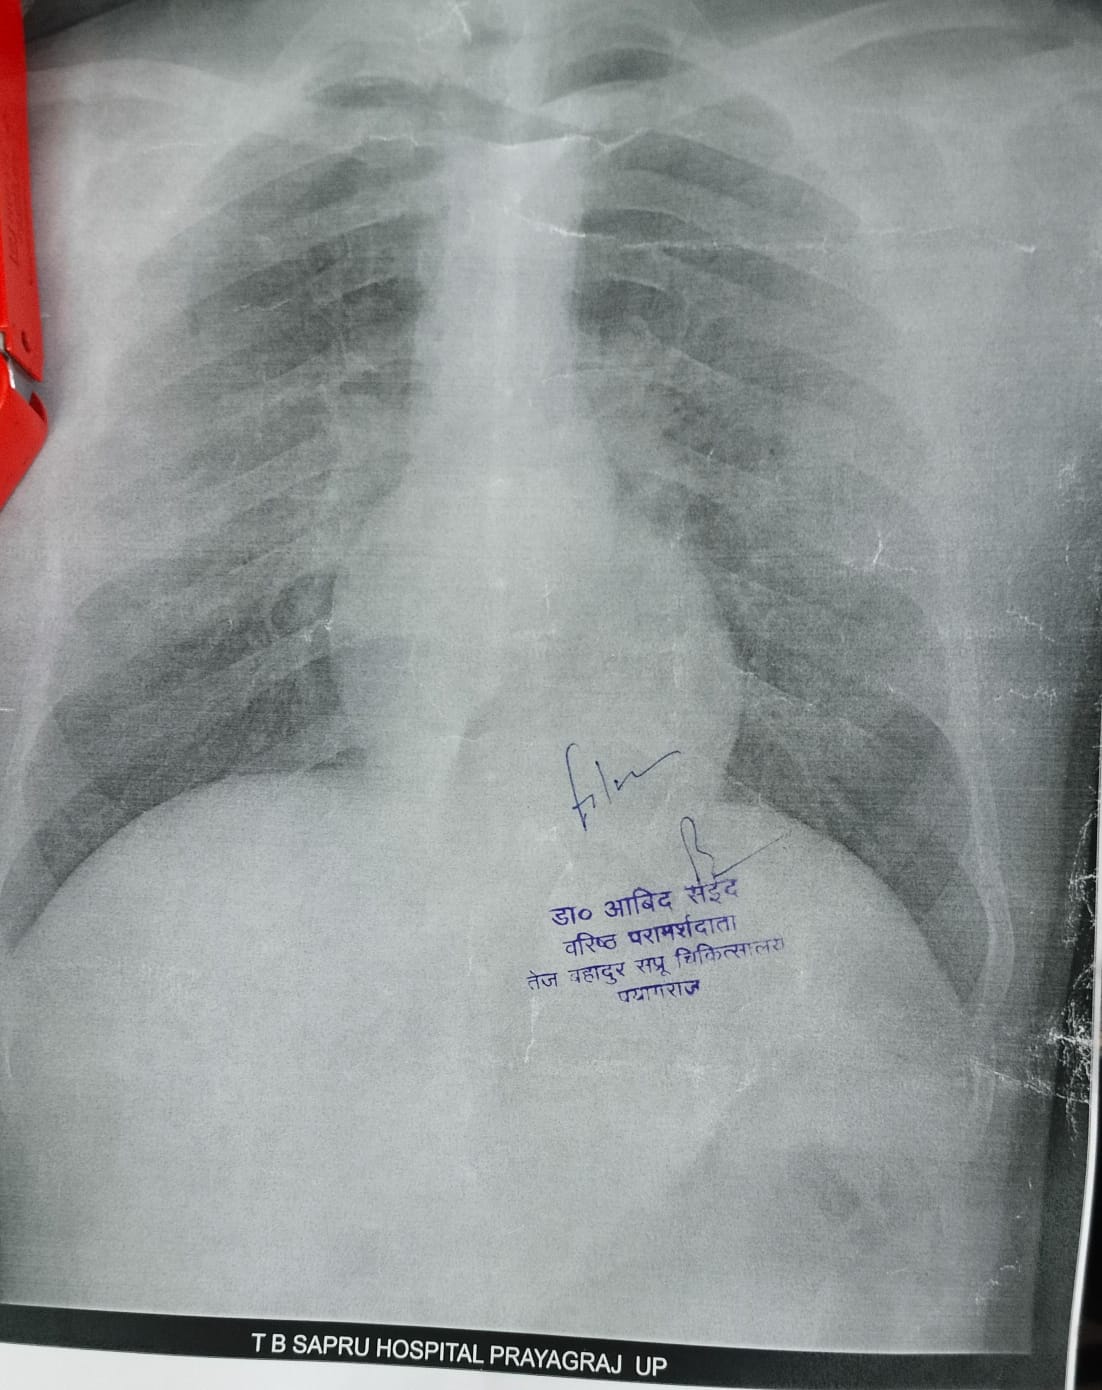

प्रयागराज के तेज बहादुर सप्रू (बेली) हॉस्पिटल में कहने के लिए डिजिटल एक्स-रे तो हो रहा है लेकिन रिपोर्ट उन्हें फिल्म पर नहीं बल्कि ए-4 साइज के सादे पन्ने पर दिया जा रहा है। ऐसे में इस डिजिटल एक्स-रे होने का फायदा क्या है। मरीज 2 से 3 घंटे तक इंतजार क

पन्ने पर रिपोर्ट लेकर डॉक्टर के पास जाता है तो पता चलता है कि हड्डी या नस में क्या दिक्कत है यह तो स्पष्ट नहीं हो पा रहा है। फिर मजबूरन मरीज को बाहर जाकर प्राइवेट सेंटर पर एक्स-रे कराना पड़ता है।

इस तरह ए-4 साइज के कागज पर दिया जा रहा है रिपोर्ट।

यदि कोई मरीज एक्स-रे कक्ष के कर्मचारियों से फिल्म पर रिपोर्ट मांगता है तो बताया जाता है कि CMS मैडम से आदेश कराएं तभी फिल्म मिल पाएगा। यहां प्रतिदिन 200 से ज्यादा एक्सरे होता है लेकिन फिल्म सिर्फ 8 से 10 लोगों को ही दिया जाता है। बाकी लोग पन्ने पर रिपोर्ट लेकर टहलते रहते हैं।